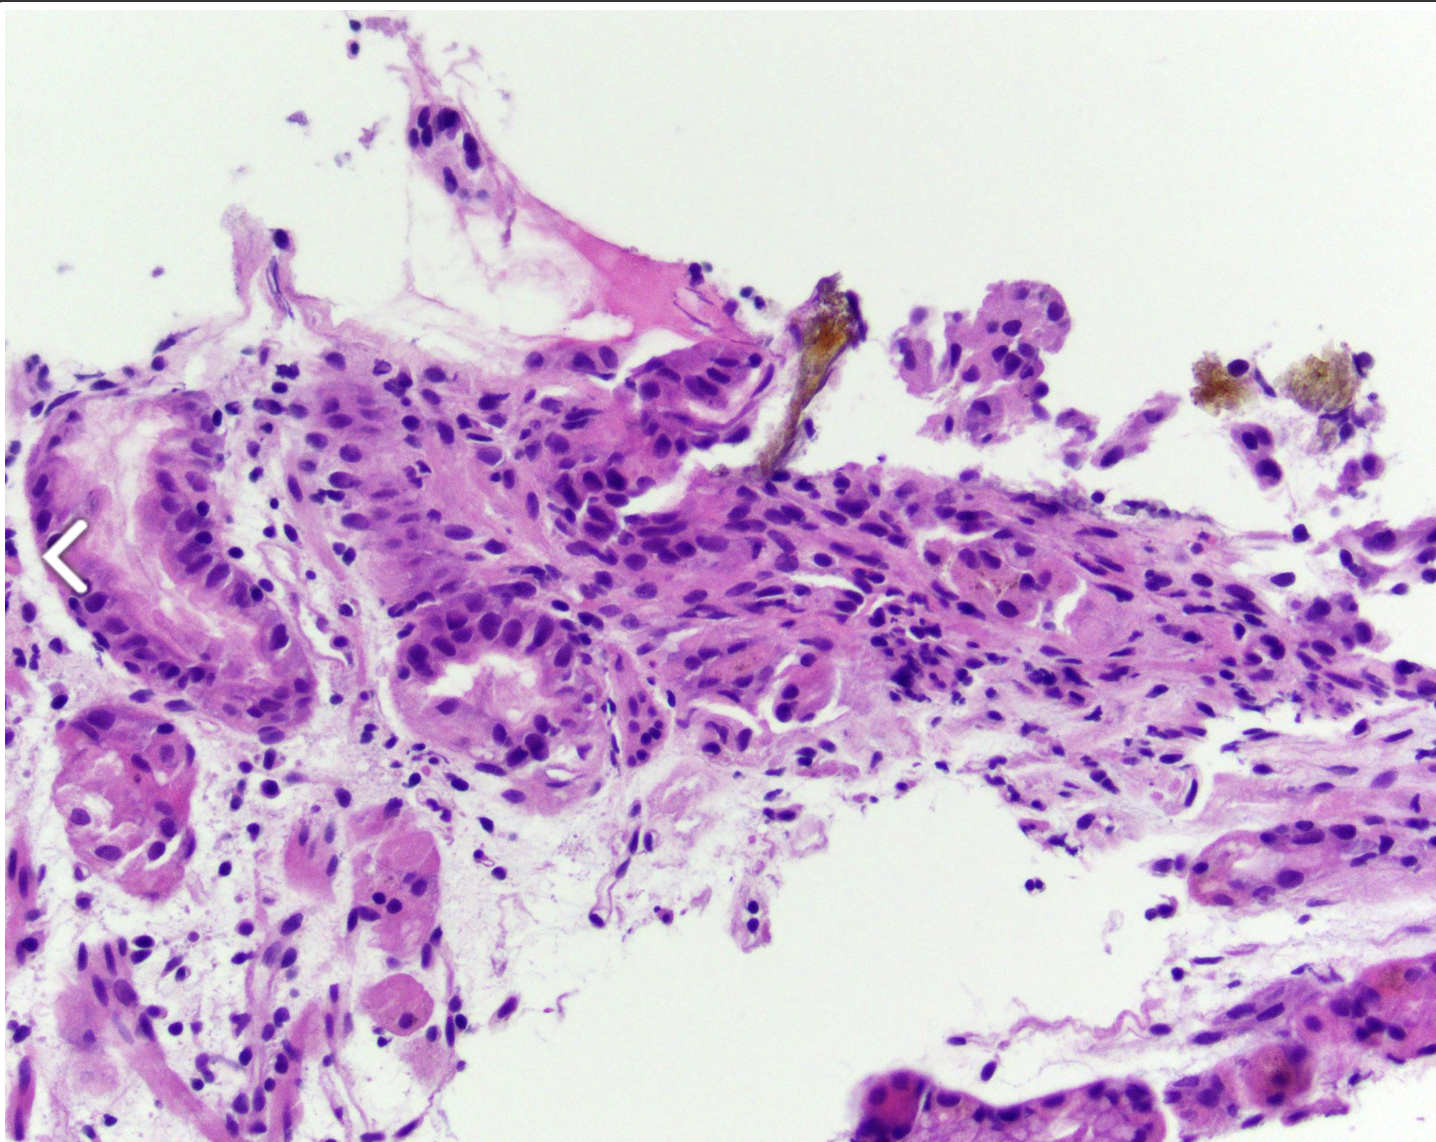

Patient avec colite

1) diagnostic

2) histologie

1) entamoeba histolytica

2)

ulcère en forme de flasque (photo)

Cytoplasme PAS+

erythrocytes phagocytes